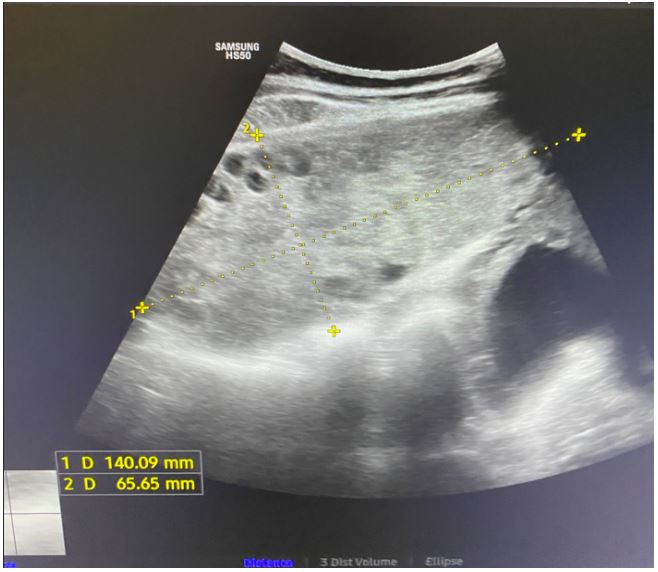

Transabdominal ultrasound identified intrauterine MCMA twin pregnancy. The right ovary measured 14x6.5x9.7 cm with multiple peripherally displaced ovarian follicles resembling a string of pearls (Figures 3 and 4). The left ovary measured 12x7x9.1 cm also with peripheral follicles and stromal oedema (Figure 5). In both ovaries, there was an absent doppler flow. In the region of the right adnexa, there was a collection of free fluid up to 8 mm (Figure 3). Umbilical arterial (UA) Doppler assessment was used in the surveillance of fetal well-being, which showed good fetal condition (Figures 6 and 7).

Figure 5: Abdominal ultrasound: Left ovary that shows enlargement and stromal oedema.